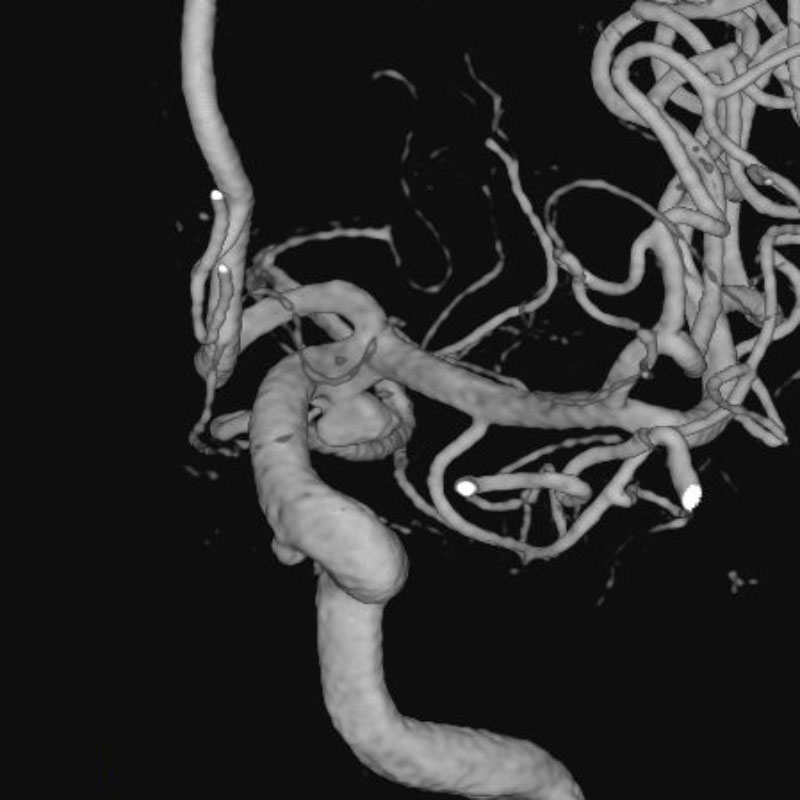

脳動静脈奇形

血管塞栓術

松田/濵田/元永